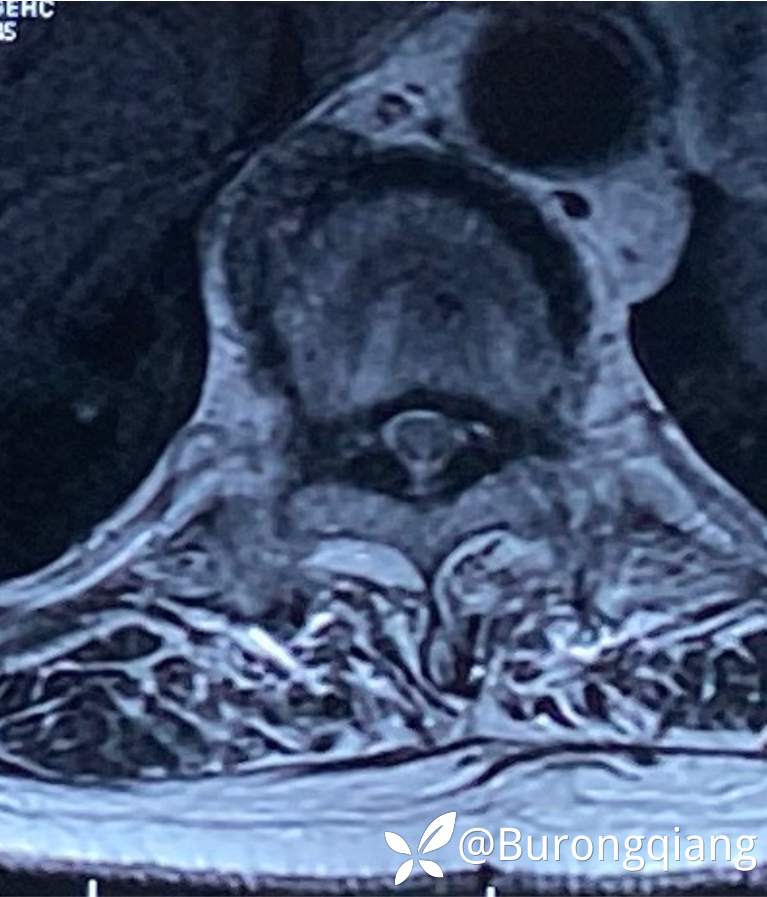

简要病史:患者述2年前无明显诱因出现双下肢大腿憋胀不适症状。外院进一步检查后诊断胸腰椎椎管狭窄,于外院行胸腰椎多节段椎管减压内固定手术治疗,术后症状改善明显,术后10个月再次逐渐出现双下肢麻木无力症状,左侧症状明显,行走时偶有打软腿不适,1年前摔倒致左踝关节骨折,给予内固定手术治疗,术后一直未能下地活动,双下肢麻木无力明显,二便正常。采取保守对症治疗,症状近来逐渐加重。

临床诊断:胸椎管狭窄

治疗经过:给予脊柱内镜下椎管扩大减压手术治疗。